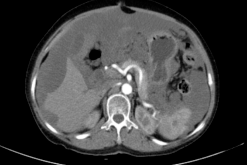

贾栋院长为一个脑肿瘤患者做手术,明确病因,分析肿瘤位置,但由于肿瘤比较大,位于重要的功能区,周围血管神经复杂。生死一线,贾栋院长给患者实施创伤小、恢复快的经鼻蝶微创手术,借助神经内镜技术,通过鼻腔天然的通道,直接抵达肿瘤部位,从而做到全切肿瘤,一朝解除了患者的病痛。